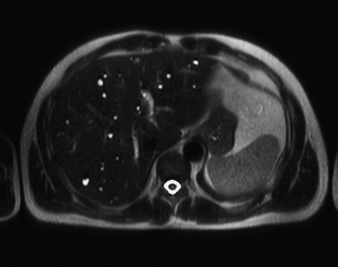

RM Pelvis

Prueba diagnóstica no invasiva que consiste en la obtención de imágenes de alta definición anatómica de la pelvis mediante el empleo de un campo electromagnético y ondas de radio (con un emisor y un receptor). No utiliza radiación ionizante. Se realiza para estudiar patologías del útero, del ovario, de las trompas y la vagina, ya sean de origen tumoral, inflamatorio o vascular. Esta prueba permite valorar órganos como la vejiga urinaria, la unión entre los uréteres y la vejiga, la próstata, las vesículas seminales, la uretra, los huesos de la pelvis, etc A veces requiere el uso de contraste intravenoso (Gadolinio) para caracterizar las lesiones.